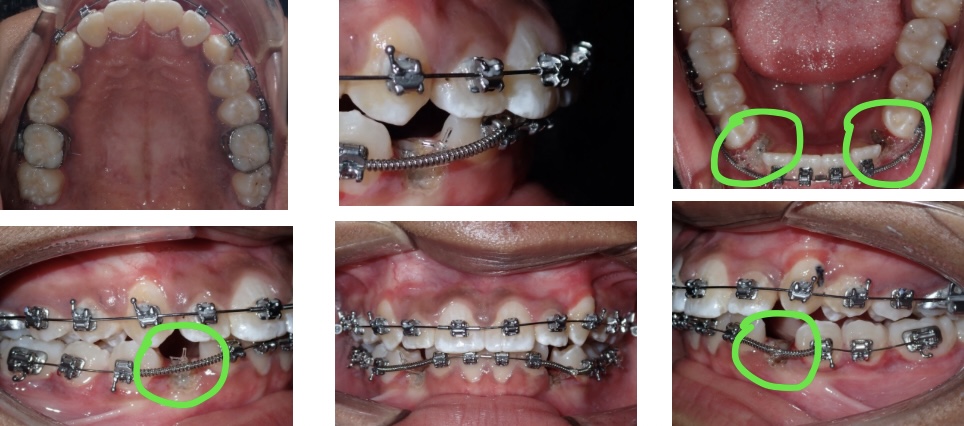

The Process. During this procedure, Lauren’s mouth was numbed. The periodontist or oral surgeon makes his/her way through the gum tissue and bone and glues a small button on the tooth. The button is then attached to a short gold chain. Back at the orthodontist office, we attach this chain to the wire of Lauren’s braces. Over a series of visits, we slowly pull the teeth closer and closer until we can finally see them poke through the gum tissue! Take a look at the highlighted areas below to see the areas where we slowly encouraged Lauren’s teeth to the correct positions.

Results. Once the canine teeth have fully erupted, we place full braces on the teeth until they are straightened and in line with the rest of her teeth. The x-ray below shows the canine teeth, now in the corrected positions.